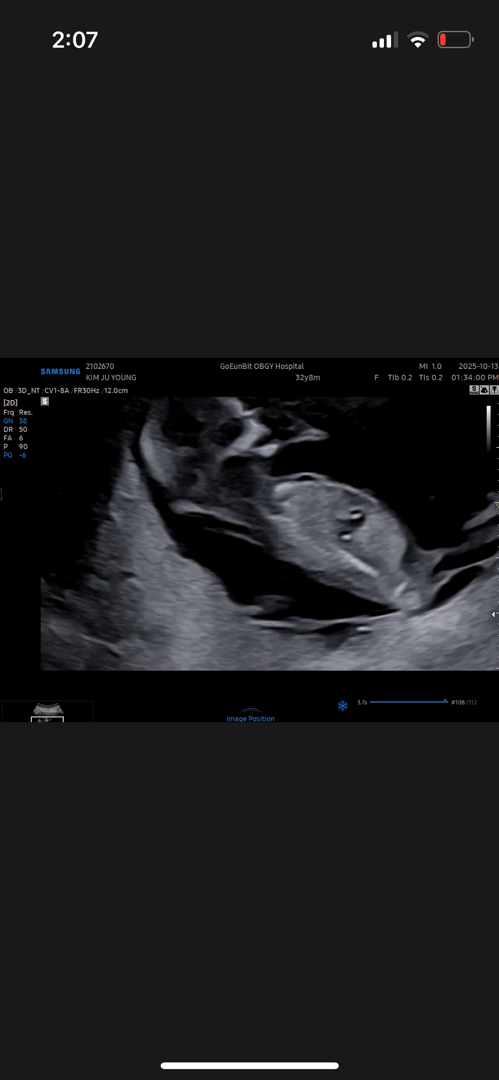

성별 투표: 12주0일차 사진❤️

시간되시면 저도 투표 한번씩 부탁드려요...🫶🏻🥹🙏🏻